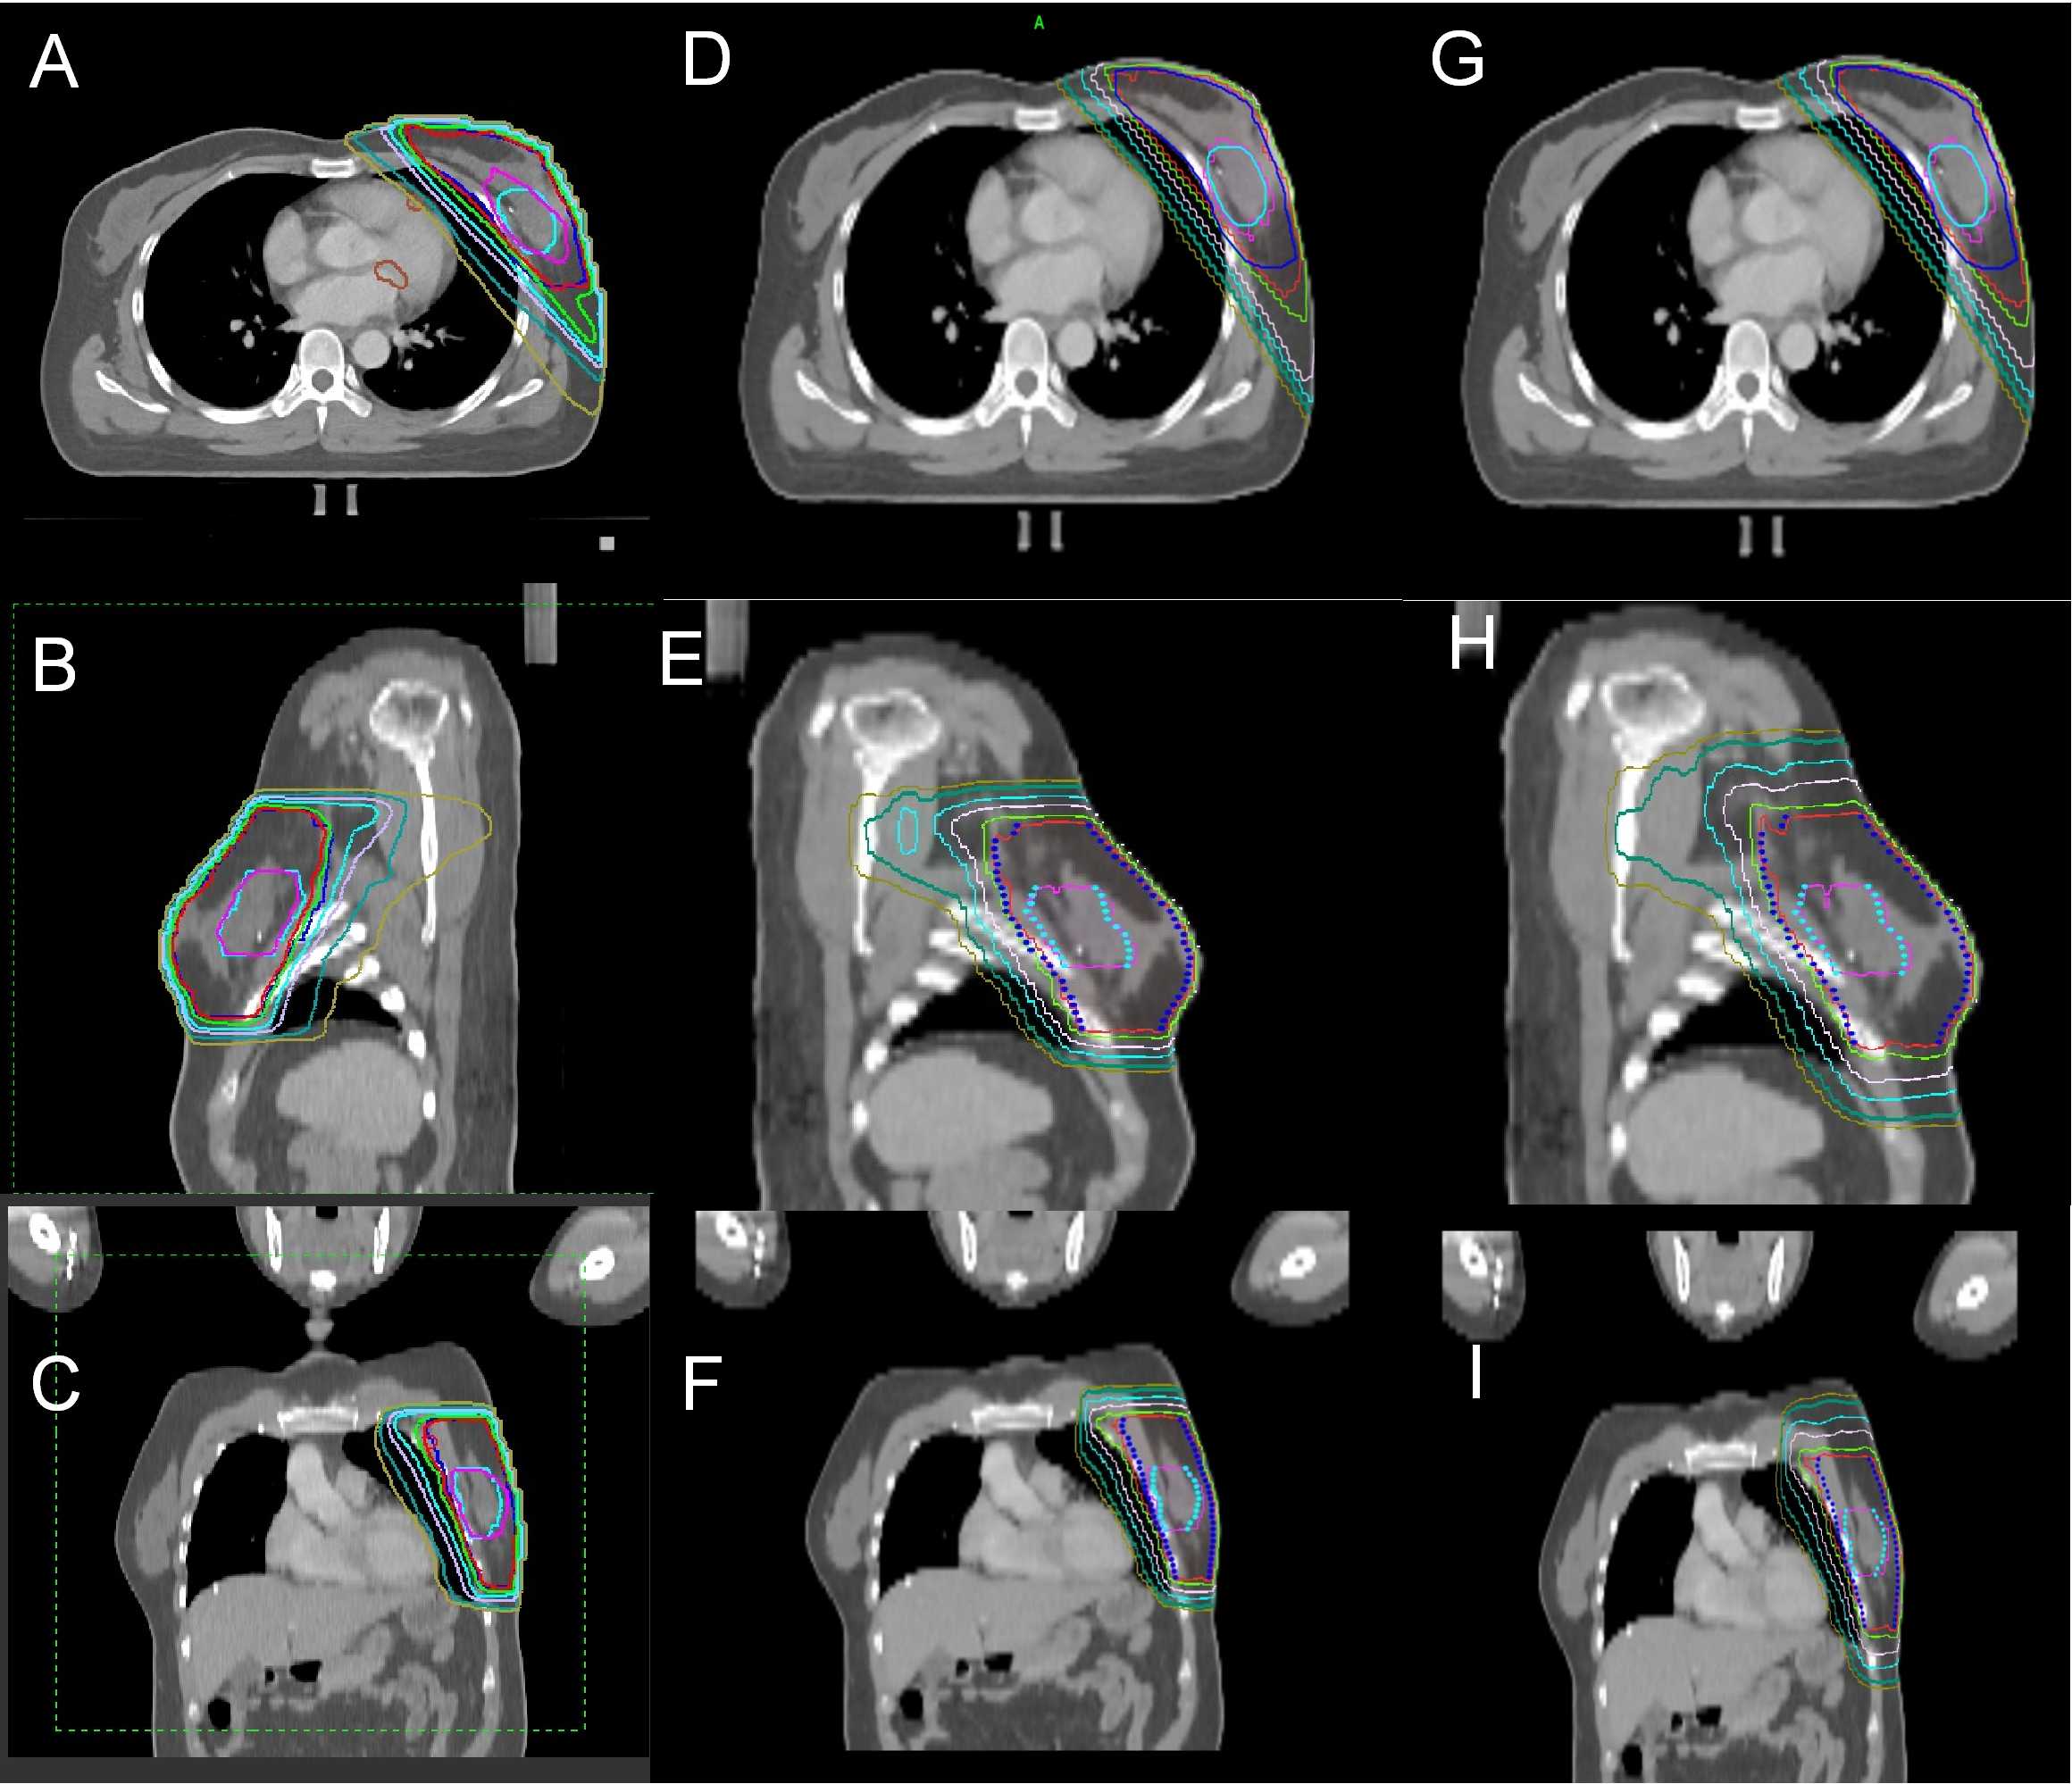

Fig. 1 illustrates the dose distributions for IMRT, TD (FW = 5 cm), and TD (FW = 2.5 cm) for one patient. The dose constraints of the target area and OAR are shown in Table 1.

Fig. 1.

Dose distribution comparison for IMRT, TD (FW = 2.5 cm), TD (FW = 5 cm). (A–C) represent axial, sagittal, and coronal slices of IMRT, respectively. (D–F) represent axial, sagittal, and coronal slices of TD (FW = 2.5 cm), respectively. (G–I) represent axial, sagittal, and coronal slices of TD (FW = 5 cm), respectively. The pink line represents 49.5 Gy, the red line represents 43.5 Gy, the green line represents 40 Gy, the light purple line represents 30 Gy, the light blue line represents 20 Gy, the dark teal line represents 9 Gy, and the light brown line represents 5 Gy. The light green area at the center of the dose lines represents the PGTV, while the blue area represents the PTV. IMRT, intensity-modulated radiotherapy; PGTV, planning gross target volume; PTV, planning target volume; FW, field width; TD, Tomo Direct.